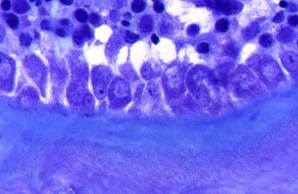

Deep Phenotyping & Histomorphometry

The section Deep Phenotyping & Histomorphometry is focused on the detailed and in-depth analysis of osteological in vivo and in vitro models. These investigations give raise to comprehensive knowledge that allows drawing conclusions on basic process in skeletal biology and pathomechanisms of specific musculoskeletal disorders.

Through the application of a combination of innovative and classical methods of osteological research, we are able to address even the most challenging scientific questions. A special focus is on histomorphometry, the structural and cellular measurement of osteological sections.

Due to the close relation to the other working groups and the patient care of the department of osteology and biomechanics, our research takes place in an interdisciplinary environment with excellent translational possibilities.